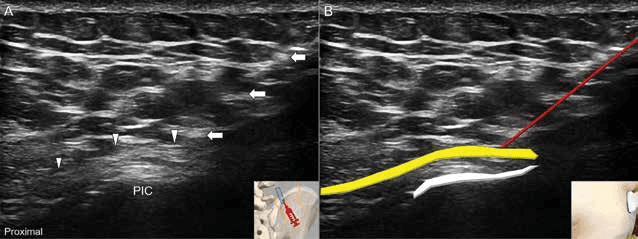

상둔신경 중간분지의 장축 영상을 통해 신경의 종방향 주행 경로를 확인했습니다. 수압박리술 - 그림 7. 상둔신경 중간분지(intermediate branches)의 장축 영상에 대한 Figure 7. 그림 7. 상둔신경 중간분지(intermediate branches)의 장축 영상에 대한 초음파 영상(A)과 개략도(B)입니다.

흉요근막 사이의 상둔신경을 목표로 하는 평면내 접근법으로 수압박리술을 시행했습니다. 수압박리술 - 그림 8. 흉요근막(thoracolumbar fascia) 사이의 상둔신경(단축 영상)을 Figure 8. 그림 8. 흉요근막(thoracolumbar fascia) 사이의 상둔신경(단축 영상)을 목표로 하는 평면내(lateral to medial) 접근법입니다.